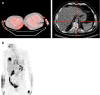

Purpose: (18)F-Labelled fluorodeoxyglucose (FDG) can detect early changes in tumour metabolism and may be a useful quantitative imaging biomarker (QIB) for prediction of disease stabilization, response and duration of progression-free survival (PFS). Standardization of imaging procedures is a prerequisite, especially in multicentre clinical trials. In this study we reviewed the quality of FDG scans and compliance with the imaging guideline (IG) in a phase III clinical trial.

Methods: Forty-four cancer patients were enroled in an imaging sub-study of a randomized international multicentre trial. FDG scan had to be performed at baseline and 10-14 days after treatment start. The image transmittal forms (ITFs) and Digital Imaging and Communications in Medicine (DICOM) [1] standard headers were analysed for compliance with the IG. Mean liver standardized uptake values (LSUVmean) were measured as recommended by positron emission tomography (PET) Response Criteria in Solid Tumors 1.0 (PERCIST) [2].

Results: Of 88 scans, 81 were received (44 patients); 36 were properly anonymized; 77/81 serum glucose values submitted, all but one within the IG. In 35/44 patients both scans were of sufficient visual quality. In 22/70 ITFs the reported UT differed by >1 min from the DICOM headers (max. difference 1 h 4 min). Based on the DICOM, UT compliance for both scans was 31.4%. LSUVmean was fairly constant for the 11 patients with UT compliance: 2.30 ± 0.33 at baseline and 2.27 ± 0.48 at follow-up (FU). Variability substantially increased for the subjects with unacceptable UT (11 patients): 2.27 ± 1.04 at baseline and 2.18 ± 0.83 at FU.